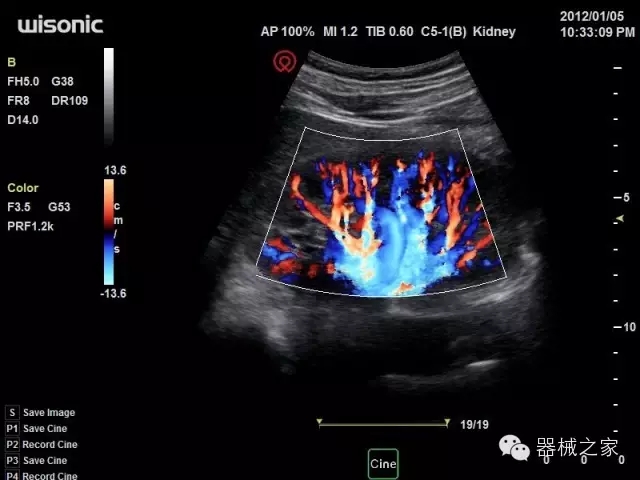

臨床圖片賞析

產(chǎn)品特點

·全球目前唯一一款配備主機(jī)雙探頭接口,整機(jī)重量(含電池)在5公斤以內(nèi)的便攜式彩超;

·一款互聯(lián)網(wǎng)彩超,只要有手機(jī)信號的地方就可以非常方便地實現(xiàn)遠(yuǎn)程會診和病案調(diào)??;

·鎂鋁合金外殼,堅固可靠耐用;

·獨有的HoloTM PW 實時3取樣門PW成像技術(shù),精確進(jìn)行血管診斷;

·一鍵優(yōu)化B、Color、PW,Auto Doppler自動識別血管位置、偏轉(zhuǎn)角度等,提高工作效率;

·30°超廣角精細(xì)偏轉(zhuǎn)成像技術(shù),更優(yōu)異的頻譜圖像;

·W+智能搜索引擎,快速尋找圖像;

·SSD、USB3.0保障開機(jī)快,導(dǎo)出圖像更快,減少等待時間;

·WIFI、網(wǎng)口、3G,多重聯(lián)網(wǎng)方式,全天候保障云端備份,不再擔(dān)心圖像丟失;

·粵械注準(zhǔn)201522231208